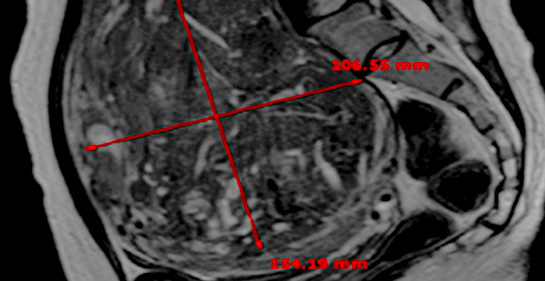

MRI촬영으로 자궁근종의 상태(위치, 개수, 크기, 모양 등), 자궁근종의 혈액공급 및 혈류, 자궁근종과 인접한 주요장기 및 구조, 초음파 발사경로의 확보 등을 분석함. 또한, 정밀초음파는 제거할 자궁근종의 개수, 자궁근종의 치료 슬라이스 수와 각 슬라이스의 체적, 근종제거마진, 근종과 인접한 장기와의 상관관계 등을 분석합니다.

시술 전 MRI검사 결과를 바탕으로 자궁근종이나

자궁선근증 등 종양의 위치, 크기, 모양 등 정확하게 파악